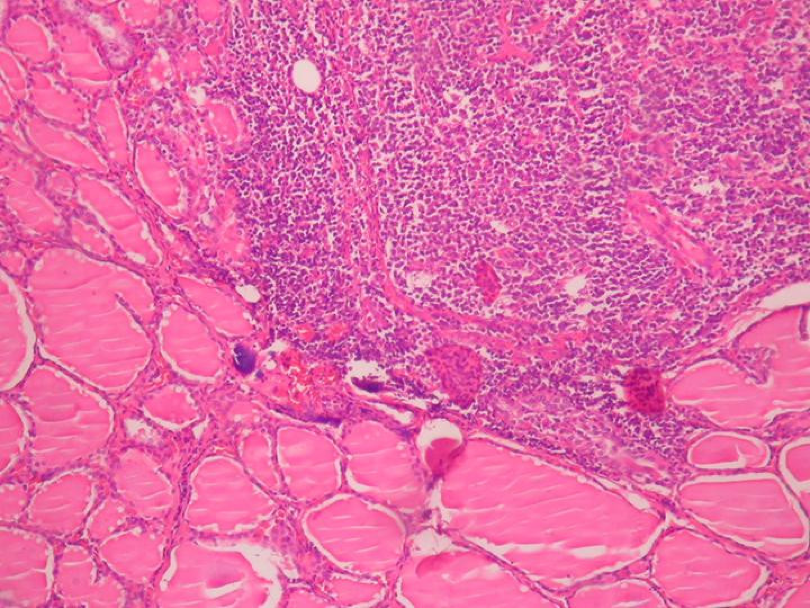

What is happening here?

In subacute lymphocytic thyroiditis, there is more follicle destruction seen but less inflammation, germinal centers, and fibrosis than Hashimoto’s